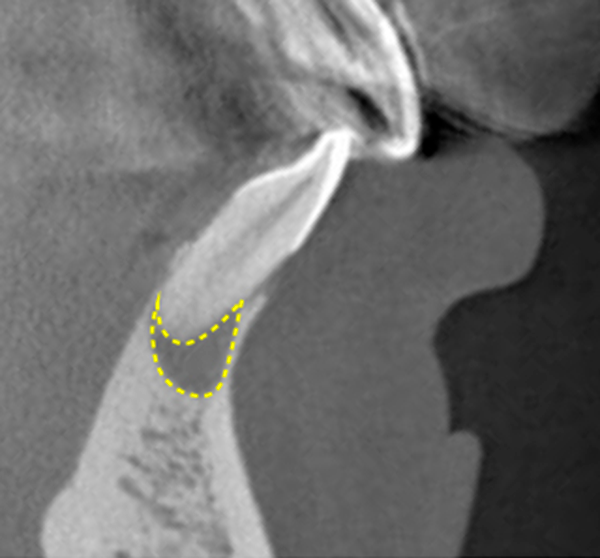

Bacteria that have reached the pulp will travel through the root canal, the cavity where the pulp used to be, to the the root apex, and finally proliferate in the bone that supports the tooth (Fig. 8).

This is called a "periapical lesion" (Fig. 9), and when this occurs, the tooth begins to move easily.

- Teeth with severely resorbed or fractured tooth-supporting bone(approximately 2/3 resorbed). (Figures 13 and 14)